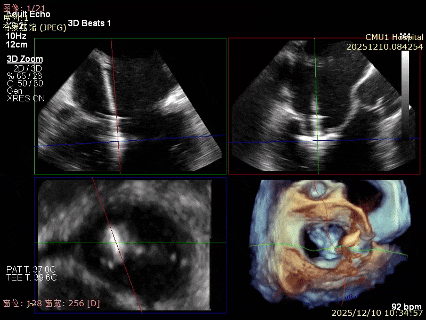

3D-Zoom下观察组织桥稳定,内侧残余脱垂

超声评估后决定释放第二枚夹子,继续在其内侧植入第三枚XTR

最终结果3D-Zoom-color显示组织桥稳定,原脱垂区域前后叶对合部分的脱垂已消除,反流降至1+以下

夹子释放Bi-com切面显示残余反流情况